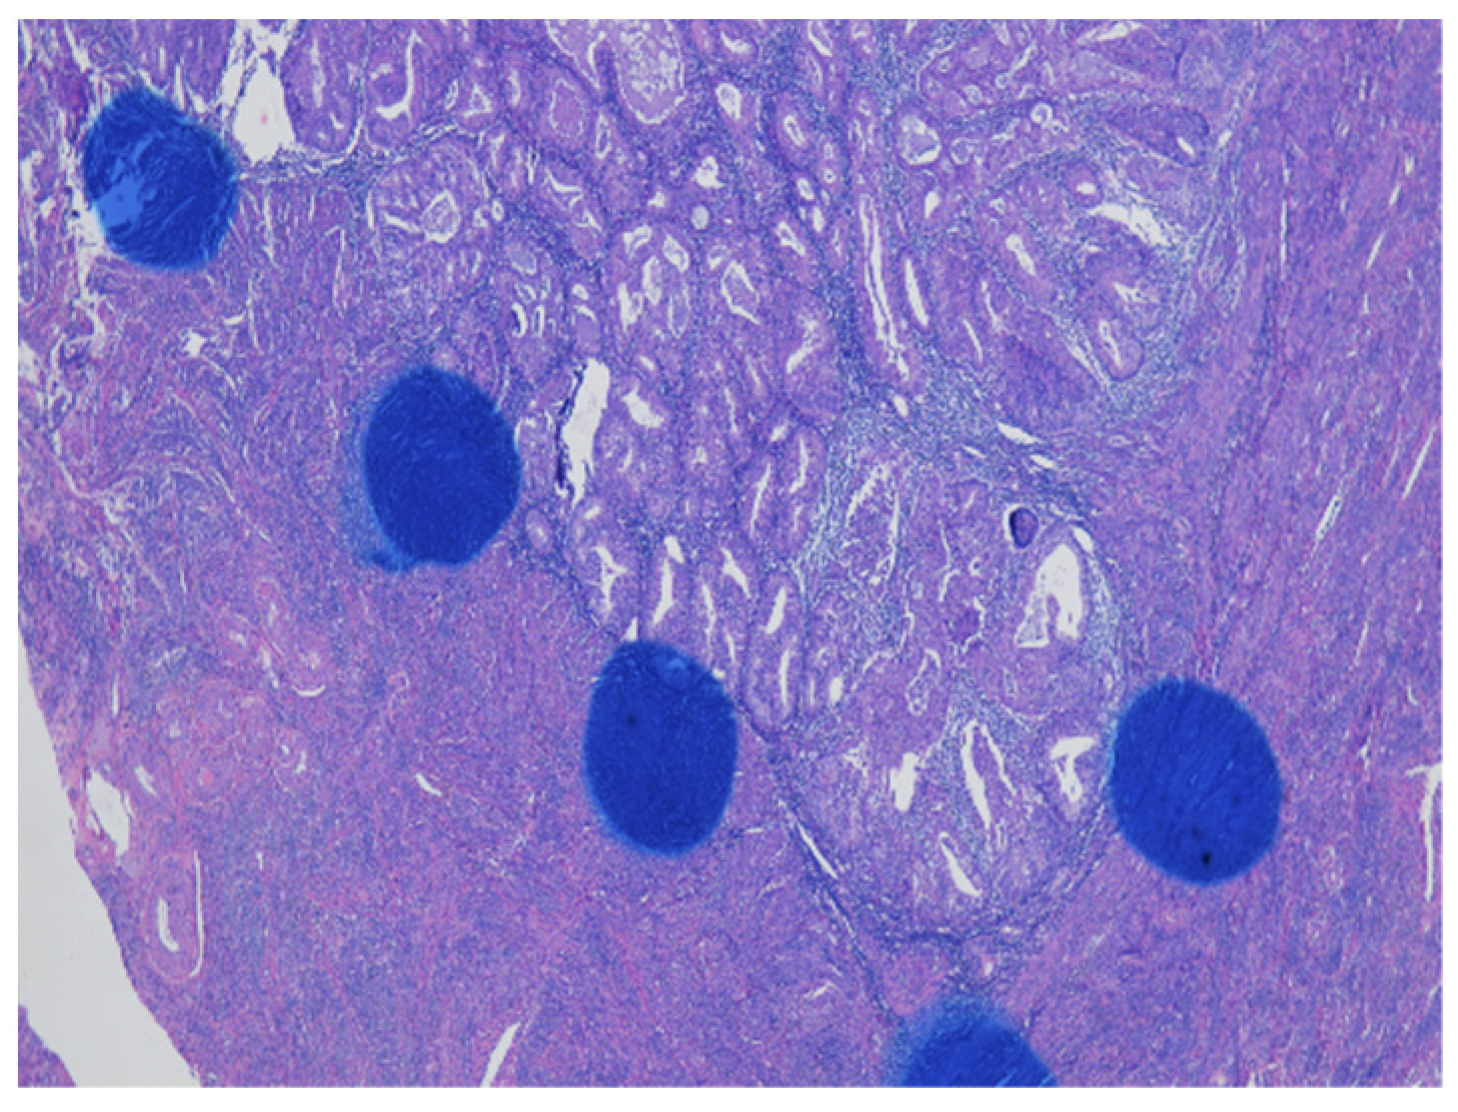

As shown in Figure 1 of EC at the uterine cornus, negative MI was found with an intact thin rim of stroma between the tumor–myometrium junction on the left side and with positive MI featuring an absence of stroma between the junction on the right side. A further higher power scope of the left side and right side of Figure 1 is shown in Figure 2 and Figure 3, respectively. Figure 2 demonstrated a thin rim of endometrial stroma between the tumor-myometrium junction (dark blue area: dark blue nuclei of stromal cells), and Figure 3 revealed the superficial early MI. MI determined by histopathology was the gold standard for comparison.

Figure 1.

Endometrial cancer at the cornus. Intact tumor–myometrial junction without myometrial invasion at the left side. Myometrial invasion without stroma presence between the junction at the right side (100× magnification).